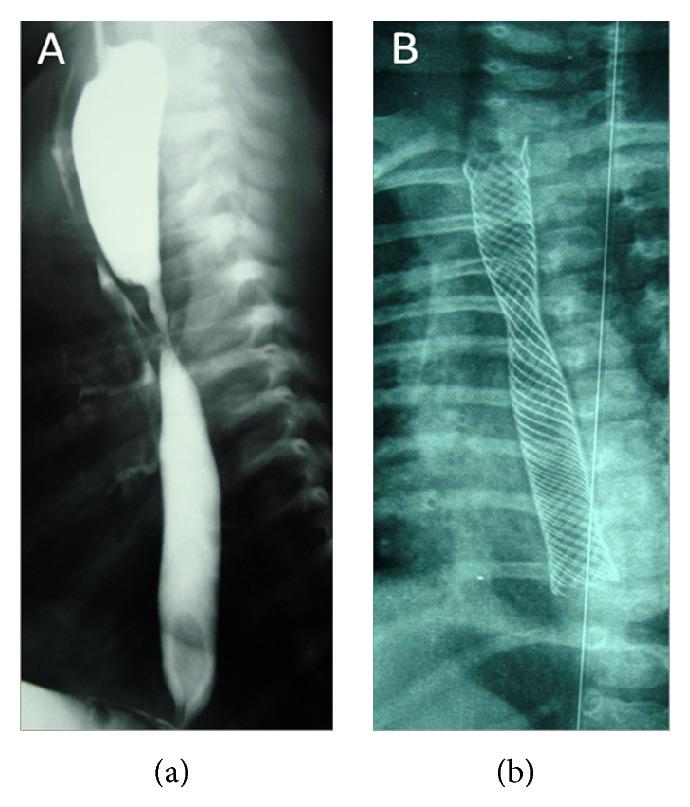

Anastomotic stricture (AS) and recurrent tracheoesophageal fistula (TEF) are two complications of surgical repair of esophageal atresia (EA). Therapeutic endoscopic modalities include stenting, tissue glue, and clipping for TEF and endoscopic balloon dilation bougienage and stenting for esophageal strictures. We report herein a two-month infant with both EA and TEF who benefited from a surgical repair for EA, at the third day of life. Two months later he experienced deglutition disorders and recurrent chest infections. The esophagogram showed an AS and a TEF confirmed with blue methylene test at bronchoscopy. A partially covered self-expanding metal type biliary was endoscopically placed. Ten weeks later the stent was removed. This allows for easy passage of the endoscope in the gastric cavity but a persistent recurrent fistula was noted. Instillation of contrast demonstrated a fully dilated stricture but with a persistent TEF. Then we proceeded to placement of several endoclips at the fistula site. The esophagogram confirmed the TEF was obliterated. At 12 months of follow-up, he was asymptomatic. Stenting was effective to alleviate the stricture but failed to treat the TEF. At our knowledge this is the second case of successful use of endoclips placement to obliterate recurrent TEF after surgical repair of EA in children.

吻合口狭窄(AS)和复发性气管食管瘘(TEF)是食管闭锁(EA)手术修复后的两种并发症。治疗性内镜治疗方法包括用于TEF的支架置入、组织胶和夹子,以及用于食管狭窄的内镜球囊扩张探条扩张术和支架置入术。我们在此报告一名患有EA和TEF的两个月大婴儿,其在出生第三天接受了EA手术修复,术后受益。两个月后,他出现吞咽障碍和反复的胸部感染。食管造影显示有AS,支气管镜检查用亚甲蓝试验证实有TEF。在内镜下放置了一个部分覆盖的自膨式金属胆道支架。十周后取出支架。这使得内镜能够轻松进入胃腔,但发现有持续性复发性瘘管。注入造影剂显示狭窄已完全扩张,但仍有持续性TEF。然后我们在瘘管部位放置了几个内镜夹子。食管造影证实TEF已闭塞。在12个月的随访中,他没有症状。支架置入有效地缓解了狭窄,但未能治疗TEF。据我们所知,这是第二例成功使用内镜夹子置入术闭塞儿童EA手术修复后复发性TEF的病例。